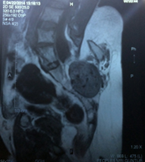

Figure 2-MRI showing a mass in the sacrococcygeal area, L4/L5 sacral anomaly with spina bifida, a few bony structures, subcutaneous fat, muscle elements and a bowel segment overlying the sacrum

- A plain MRI of the lower lumbosacral region revealed an L4/L5 block vertebral anomaly of the sacrum with spina-bifida.

- Few other features like subcutaneous fat, a few rudimentary bone structure, a few muscular elements and a well-defined saccular structure showing a pocket of air, resembling a bowel, overlying the sacrum.

- There was no gross anomaly noted in the pelvis region. Ultrasound showed abnormality too. Alfa fetoprotein levels were normal.

- Provisional diagnoses given were Sacrococcygeal Teratoma-Altman Type II. In such cases, the tumour is outside the body with a small portion inside the pelvis.